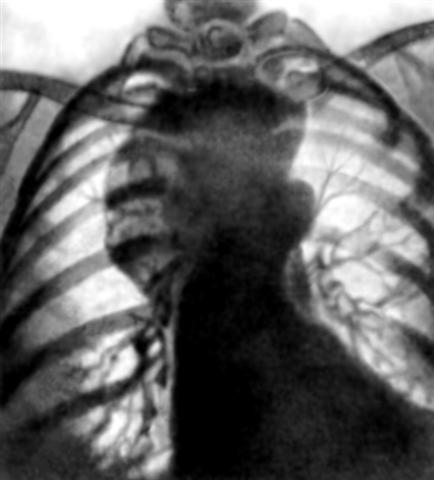

Рис. 2а). Рентгенограмма грудной клетки больной с дермоидом средостения: прямая проекция.